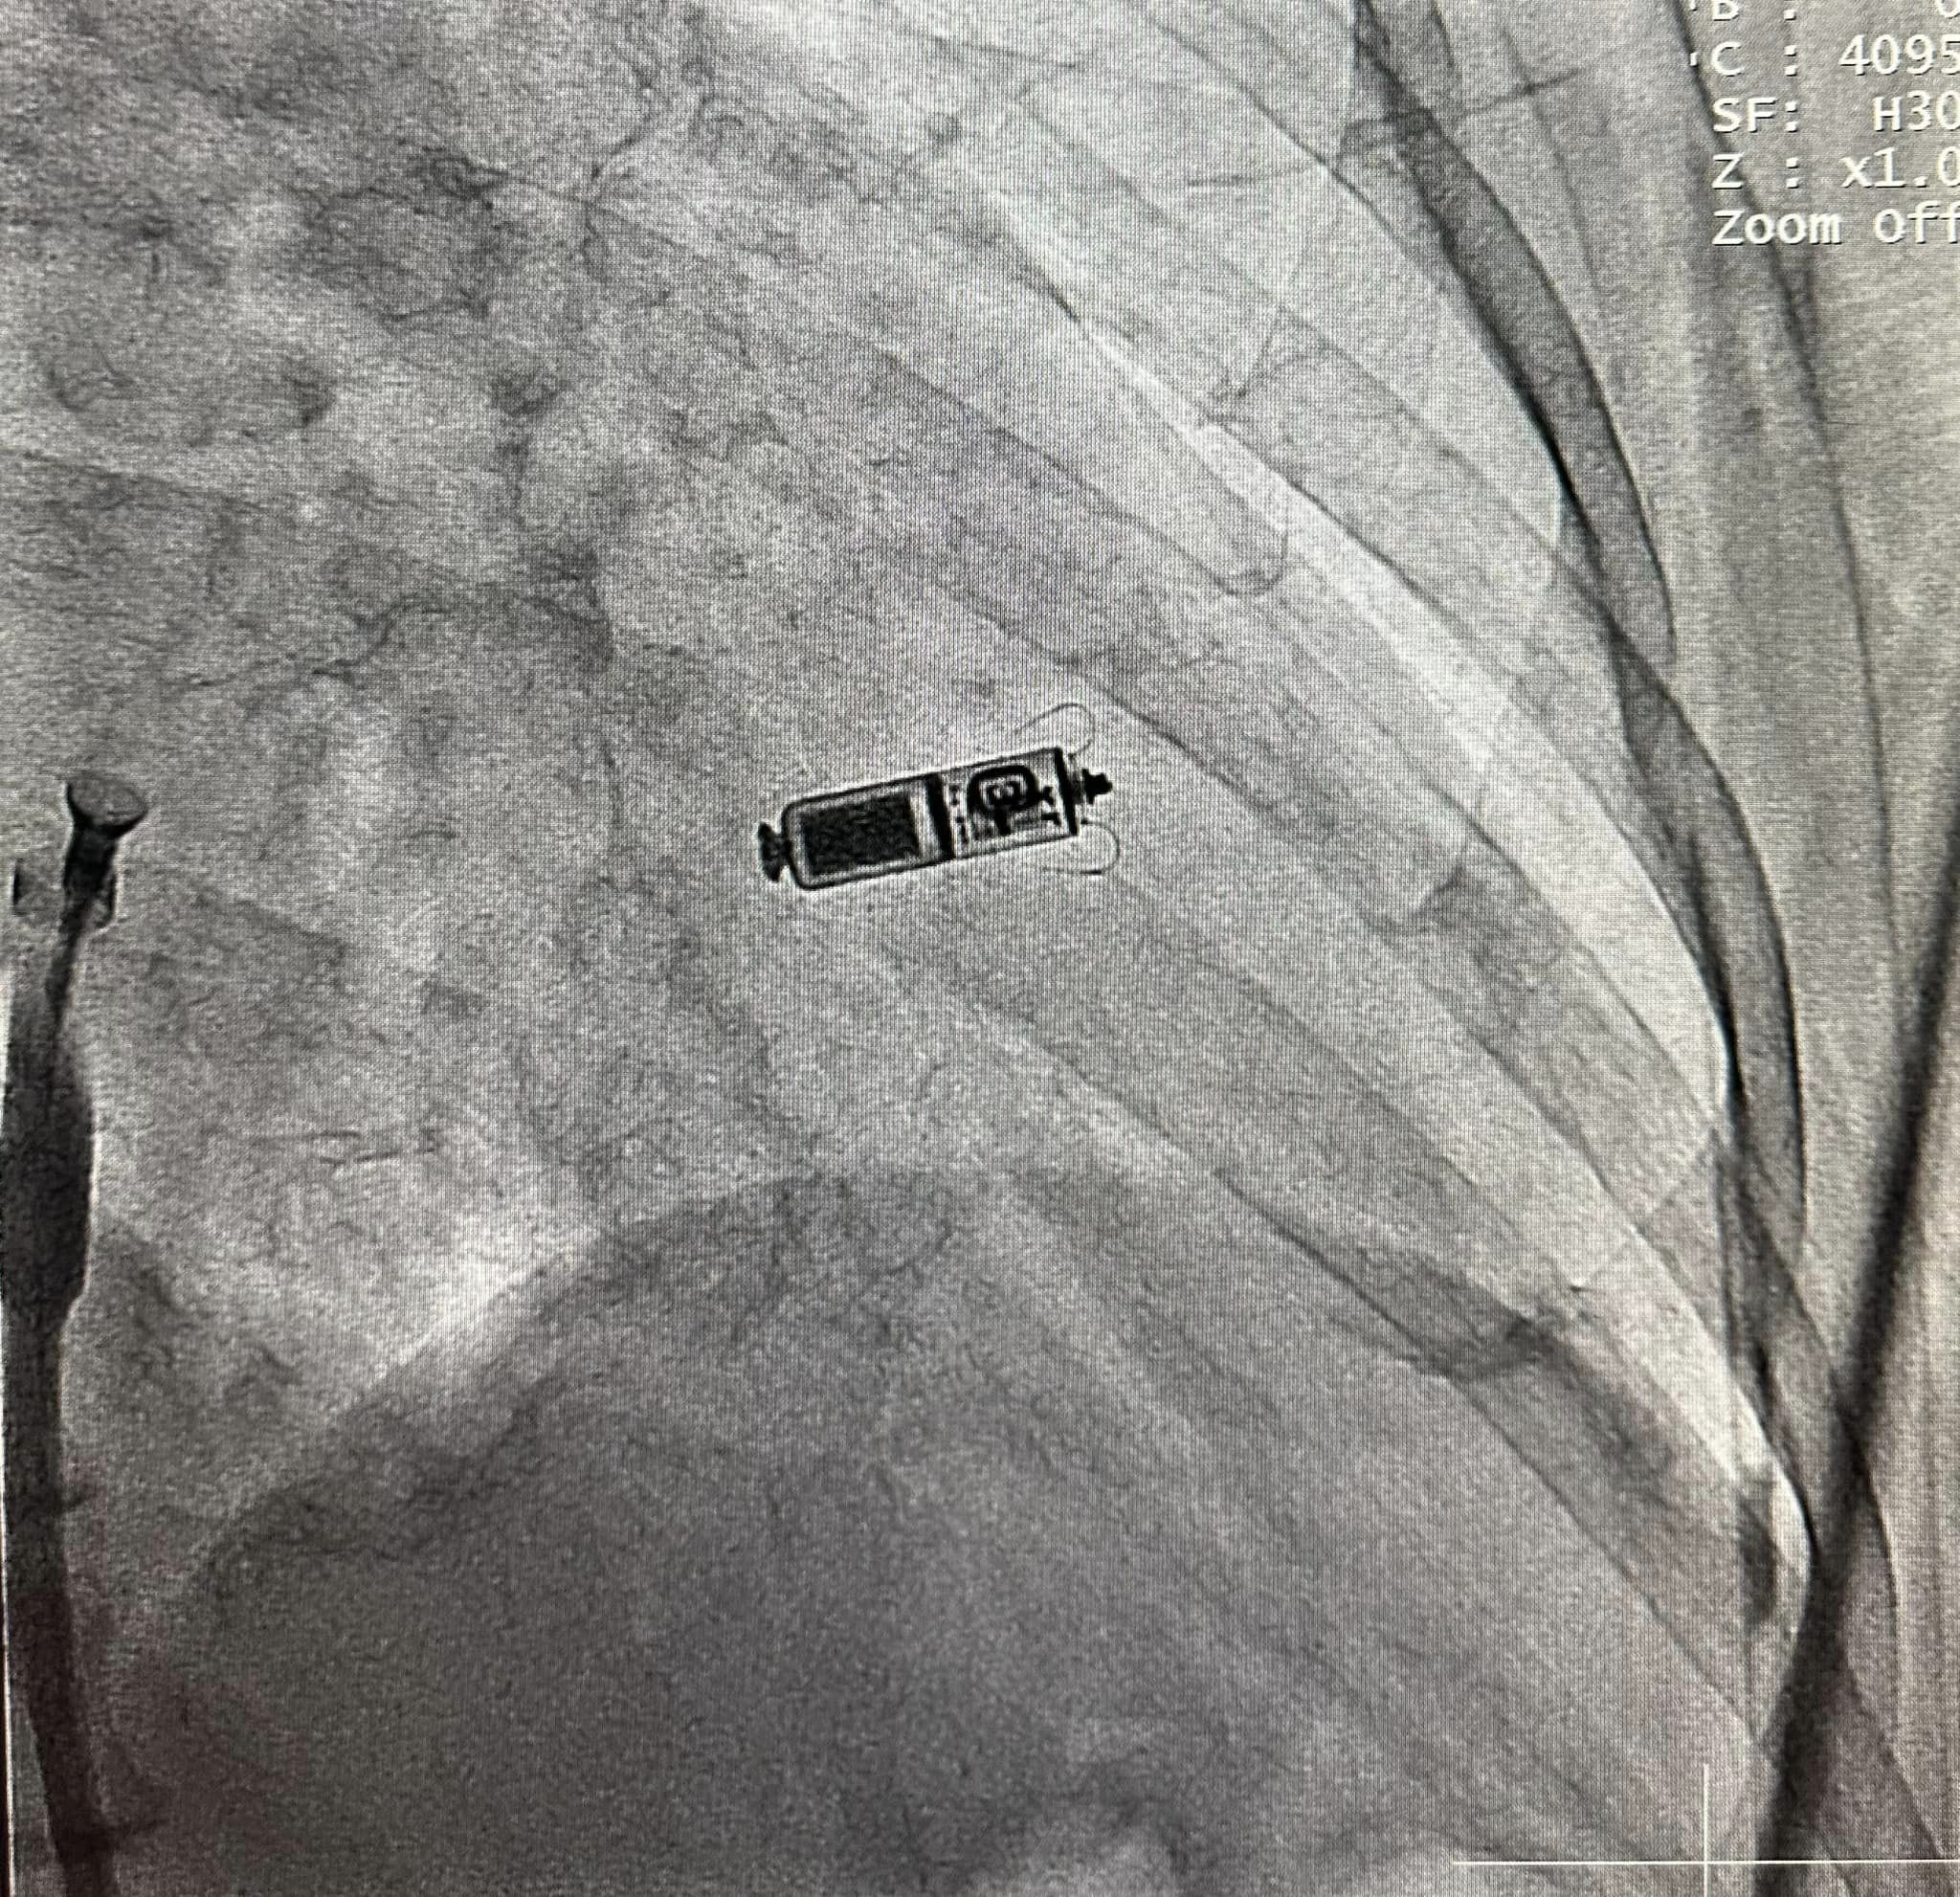

រាជធានីភ្នំពេញ៖ នៅថ្ងៃទី១៨ ខែកុម្ភៈ ឆ្នាំ២០២៣ យោងតាមការចុះផ្សាយរបស់ មជ្ឈមណ្ឌលព្យាបាលជំងឺបេះដូង និងមនុស្សចាស់ នៃមន្ទីរពេទ្យមិត្តភាពខ្មែរ-សូវៀត បានឱ្យដឹងថា នៅប្រទេសកម្ពុជាយើង ជាករណីលើកដំបូងទី១ហើយ ដែលក្រុមការងារ វេជ្ជបណ្ឌិតឯកទេសចង្វាក់បេះដូង នៅមន្ទីរពេទ្យមិត្តភាពខ្មែរ-សូវៀត បានធ្វើការដាក់ ថ្មបេះដូងតូចបំផុតមិនមានខ្សែ ជាមួយបច្ចេកទេសទំនើបចុងក្រោយ (Micra leadless pacemaker) ដោយមិនមានការវះកាត់ ជាមួយនឹងលទ្ធផលជោគជ័យ និងគ្មានផលវិបាក។

មជ្ឈមណ្ឌលជំងឺបេះដូង និងមនុស្សចាស់ សូមថ្លែងអំណរគុណ ដល់ក្រុមការងារវេជ្ជបណ្ឌិតចង្វាក់បេះដូងអាមេរិក Jeremiah Hope ដែលតែងតែចូលរួមសហការការងារលើផ្នែកចង្វាក់បេះដូង៕